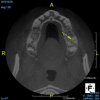

(11.) A pathosis apical to the maxillary central incisors was initially not diagnosed after evaluating the periapical film; however, the CBCT image revealed its presence. Only using the CBCT image could it be determined that the lesion was not odontogenic in origin and that it did not involve the nasopalatine foramen. This diagnosis was supported by a referral to an oral and maxillofacial radiologist.

Figure 11

(12.) A pathosis apical to the maxillary central incisors was initially not diagnosed after evaluating the periapical film; however, the CBCT image revealed its presence. Only using the CBCT image could it be determined that the lesion was not odontogenic in origin and that it did not involve the nasopalatine foramen. This diagnosis was supported by a referral to an oral and maxillofacial radiologist.

Figure 12

Are most or all dentists qualified to read CBCT images? Although the technology can be intimidating to clinicians who are not experienced in its use, the truth of the matter is that it is easier to identify structures and pathoses in CBCT images than in any 2D radiograph. This is made clear by the ability of patients to see and understand the images presented to them without receiving any formal training whatsoever. Because all dentists are trained in radiology, they can easily read a radiographic image created by a cone beam. The real issue for clinicians involves mastery of the software that their particular CBCT unit uses so that they can manipulate the images and best visualize the area in question.9 To this end, the education and training provided by the manufacturers of CBCT units can be very helpful to clinicians before they are able to gain experience through multiple evaluations of images (Figure 11 and Figure 12).

Dentists who become experienced in evaluating CBCT images become more advanced in their knowledge of anatomy as well as their familiarity with variations in normal structures. As they experience more findings, they also learn to better differentiate between normal and pathological scenarios and recognize pathoses in greater depth and detail. If dentists see something that they are not familiar with or comfortable identifying, they can refer the patient to an oral and maxillofacial radiologist.